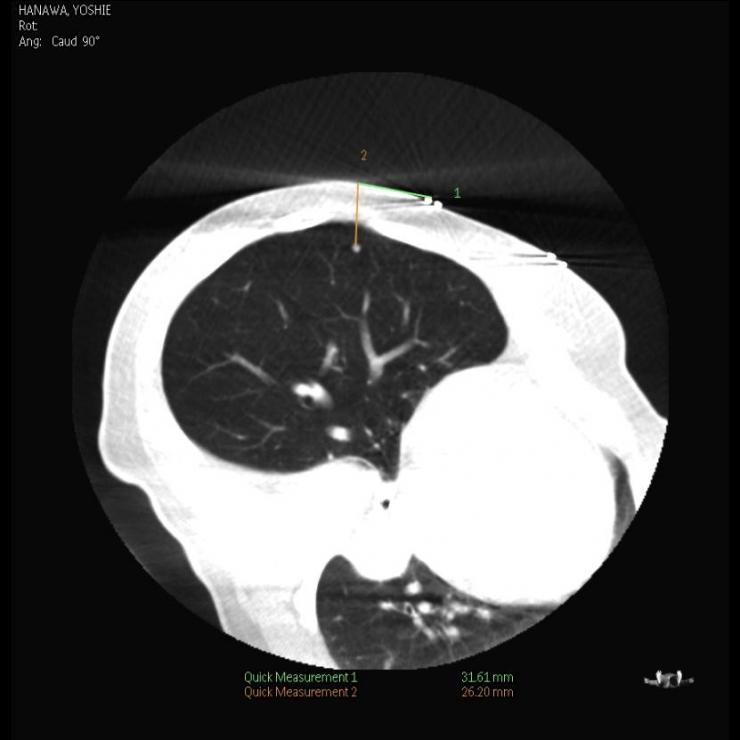

触知困難な小さな肺癌に対しても、胸腔鏡とコーンビームCTガイドを組み合わせることにより、手術中に病変を同定し切除することができます。